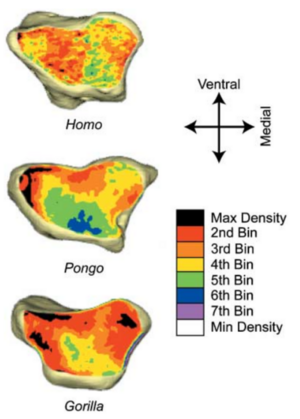

- 12.15 Habitual Use of the Primate Forelimb is Reflected in the Material Properties of Subchondral Bone in the Distal Radius